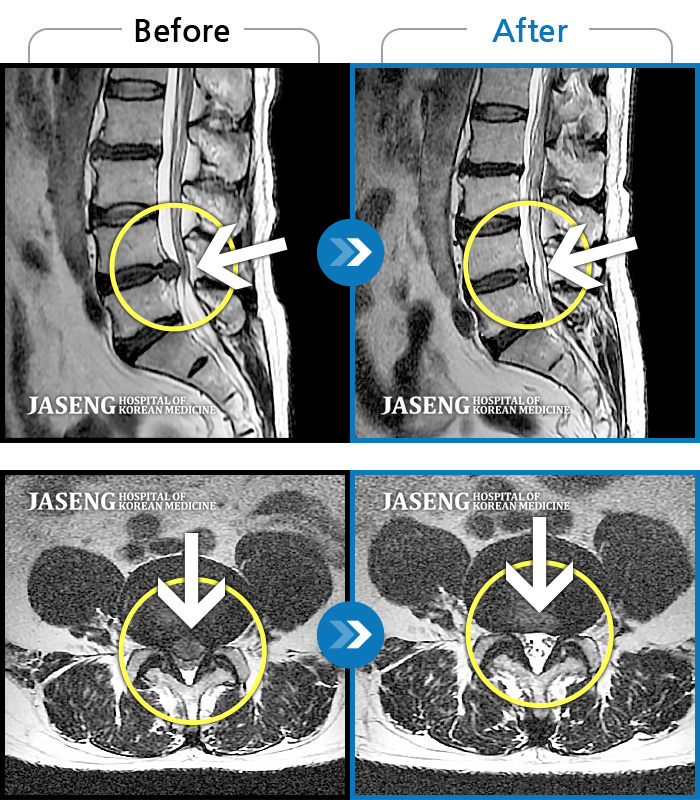

허리디스크

안산 · 김민수 원장

왼쪽 허리에서 다리로 내려가는 심한 통증으로 서 있거나 오래 걷지 못하였습니다.

촬영시기

2022.02.12 ~ 2023.02.17

2023.02.24